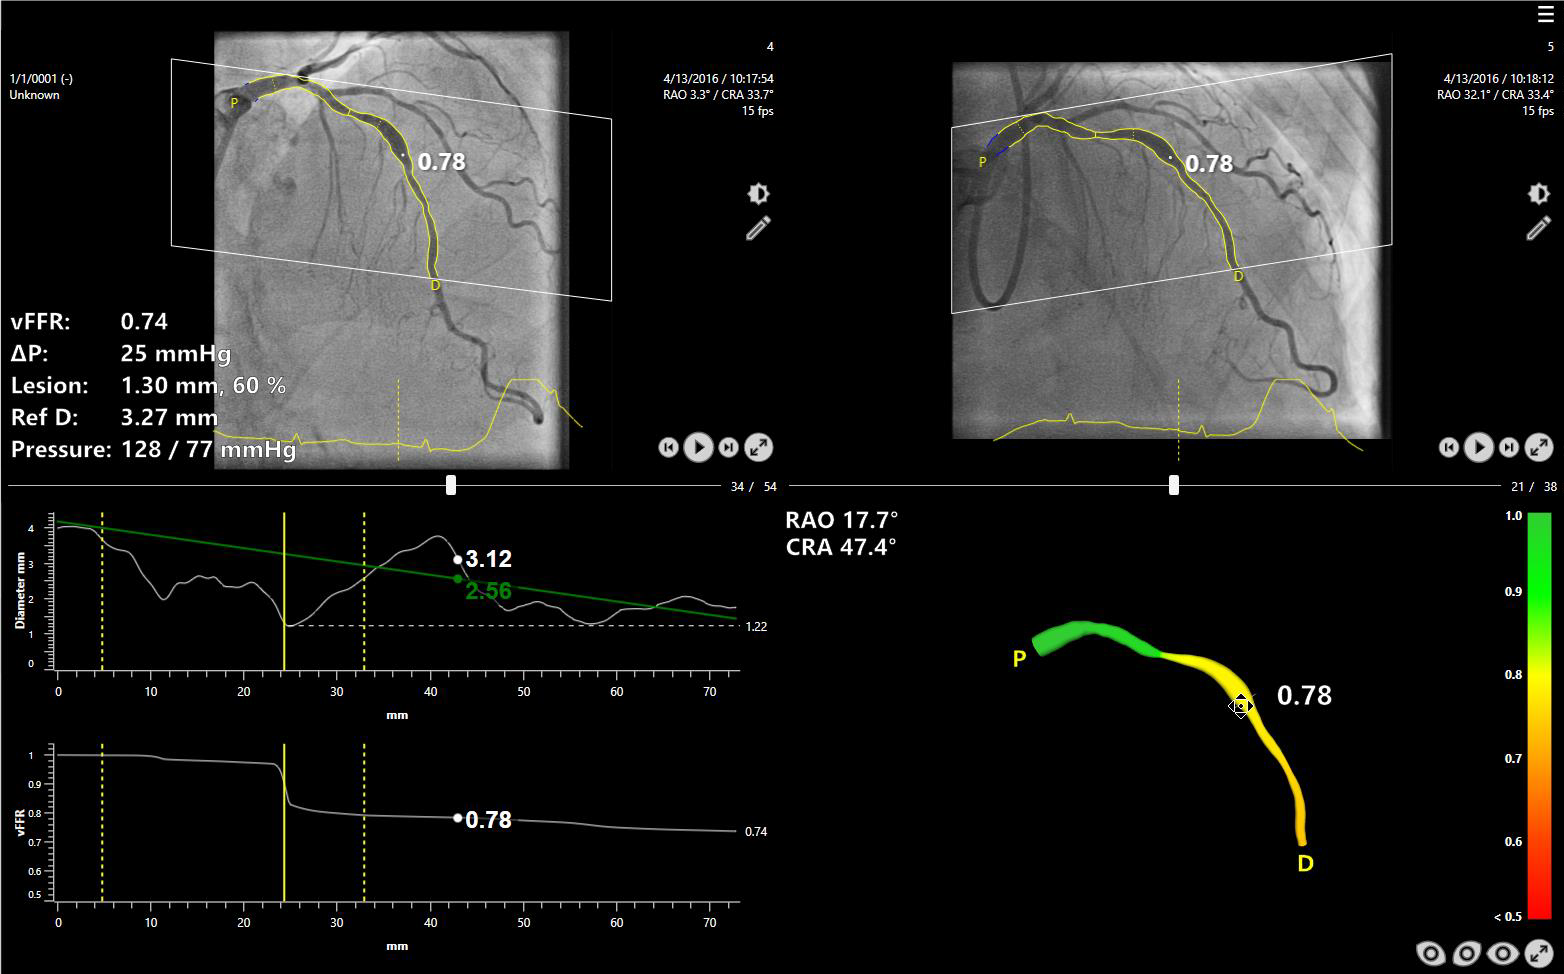

CAAS vFFR (судинний фракційний резервний кровотік, так званий віртуальний) обчислює падіння тиску в коронарних судинах без необхідності використання провідника з датчиком тиску. Модуль vFFR будує 3D-реконструкцію на основі двох ангіографій і оцінює падіння тиску, в результаті чого отримує значення vFFR. Крім того, 3D-реконструкція дозволить оцінити ступінь тяжкості та відсоток стенозу.

Інформація про функціональне ураження:

Інформація про анатомічне ураження:

Переваги: